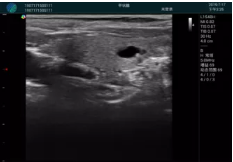

可視化穿刺引導(dǎo)

M20實(shí)時(shí)引導(dǎo):向包塊后方間隙注射利多卡因

清晰顯示腺體內(nèi)低回聲快影,邊界清晰,包膜較光滑

確定進(jìn)針路徑并實(shí)時(shí)監(jiān)測(cè)抽吸針與腫塊位置關(guān)系

抽吸針進(jìn)入腫塊內(nèi)部進(jìn)行旋切

抽吸過程中可見腫塊明顯縮小,并根據(jù)腫塊位置改變針道位置

抽吸旋切后再進(jìn)行超聲復(fù)查,原腫塊區(qū)域未見殘留組織及出血

超聲引導(dǎo)下抽吸旋切取出的腫塊組織